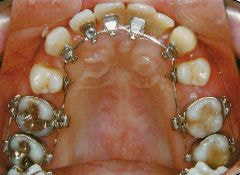

治療例2 (補綴処置+矯正)